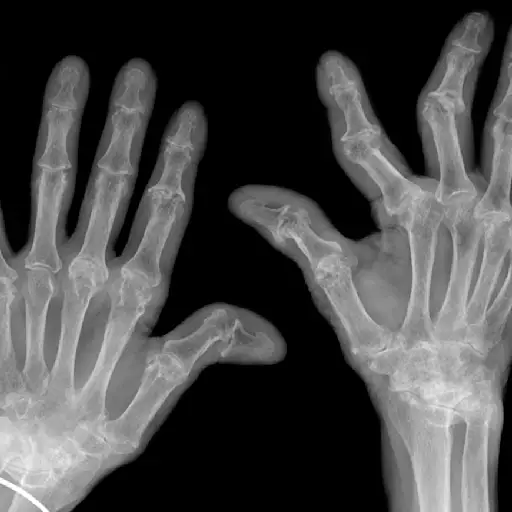

Ra从手脚开始,然后击中更大的关节

RA最常在手或脚的小关节中开始,后来延长到较大的关节,如膝盖,脚踝,肘部,臀部,肩部或颈部。在手中,Ra可以瞄准手腕或指关节(底部和中间指关节,而不是顶部接头)。在脚下,它经常发生在连接脚部到脚趾的关节中。同时,除了颈椎(颈部)外,Ra从不涉及脊柱,他补充道。另一个迹象的迹象:它通常是对称的,影响身体两侧的相同关节。

ra侵蚀骨头

另一方面,RA标志着骨果蝇的存在,丁汉博士导致骨腐蚀的细胞。严重或未治疗的RA可以导致骨骼磨损和接头移位,导致永久性随着时间的推移。尽管如此,这通常仅在严重或未治疗的RA中发生 - 并且可以通过早期诊断和适当的治疗来预防。